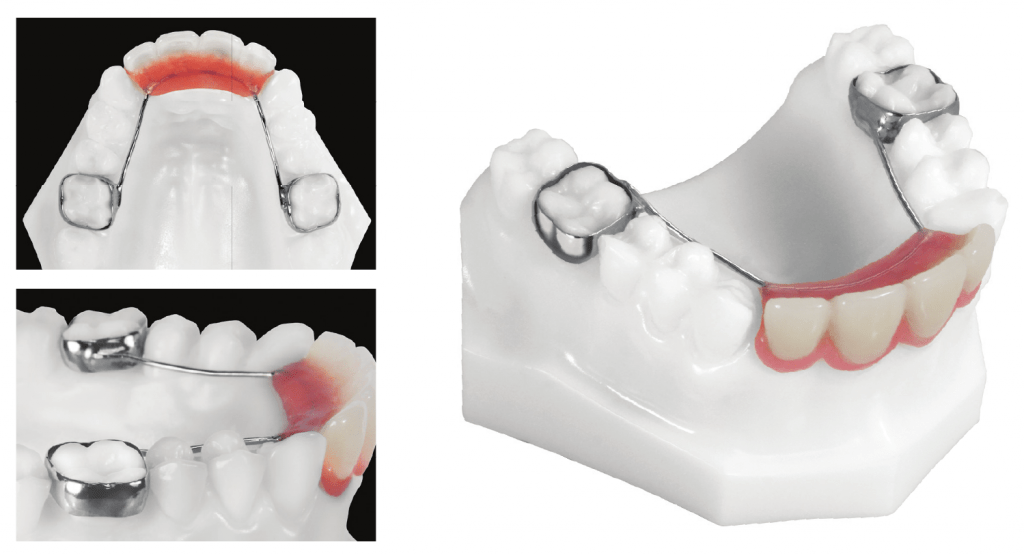

Multiple missing teeth

Nance (or transpalatal) appliance – used when there is bilateral premature loss of deciduous teeth. This appliance uses the soft tissue in rugae area as a brace to prevent the first molars from rotating and drifting mesially. This is a maxillary appliance (only) and can be utilized for anchorage.

Partial denture – can be used as a space maintainer, while also improving aesthetics and function.

Lower lingual arch – wire adapted to the lingual aspect of lower teeth. U loops allow for adjustments. Can be used for anchorage.